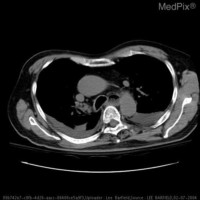

接下来使用下面三张图片进行接口测试:

分类预测:

$ img1=$(base64 -i ultrasound.jpg | tr -d '\n')

$ img2=$(base64 -i computed-tomography.jpg | tr -d '\n')

$ img3=$(base64 -i x-ray.jpg | tr -d '\n')

格式化后响应如下,第一张图片约 98% 概率为超声,第二章图片约 92% 概率为 CT,第三章图片约 99% 概率为 X 光:

{

"Clinical Photography": 0.0005052403430454433,

"Computed Tomography": 0.9238902926445007,

"Dermoscopy": 0.00016611746104899794,

"Magnetic Resonance Imaging": 0.0022810406517237425,

"Optical Coherence Tomography": 0.022591199725866318,

"Ultrasound": 0.011986842378973961,

"X-Ray": 0.03857940435409546

},